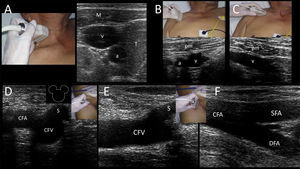

Deep veins providing access to the superior vena cava are the internal jugular vein (IJV, accompanied by the common carotid artery (CCA) in the neck), and the subclavian and axillary veins (accompanied by the corresponding subclavian and axillary arteries). Common femoral vein (CFV) (accompanied by the common femoral artery (CFA) in the groin) provide access to the inferior vena cava.

Common femoral vein (CFV)CFV is anatomically found in the groin (femoral triangle) below the inguinal ligament and medial to the common femoral artery (CFA) and femoral nerve in the neurovascular bundle. CFV is formed by the junction of the deep femoral vein and femoral vein (previously called “superficial femoral vein”) and receives the great saphenous vein (i.e. saphenofemoral junction). While CFV is usually cannulated using the anatomical landmark technique because of the relatively constant location of the vein related to the artery at a safe entry point closer to the inguinal ligament (2–4cm) 24; however, US guidance has demonstrated an 85% reduction in the rate of catheterization failure and an 86% reduction in arterial puncture rates.18 Thus, US-guided femoral cannulation is strongly recommended over the landmark technique18, and can be especially helpful in some circumstances, such as in obese patients, when arterial pulses are weak (e.g. patient is in shock) or when there are anatomical alterations.7 Ultrasonographically, this vein is easily recognized medial to the CFA and receiving the great saphenous vein. In the short axis, these structures are called the “Mickey Mouse” sign (Supplementary material, Fig. 7D). CFV is more distended when the hip has a slightly external rotation as well as in the reverse Trendelemburg position.2 In the long axis, the vein receives the great saphenous vein (Supplementary material, Fig. 7E) and its bifurcation is distal to the CFA bifurcation (Supplementary material, Fig. 7F).